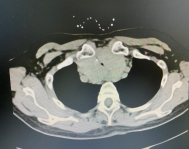

入院时CT检查

肝胆甲乳外科经CT检查,发现病人甲状腺体积明显增大,周围血管严重受压移位,气管管腔严重受压变窄,而最窄处仅约2mm左右。

2mm!也就说患者只剩下这一细若悬丝的呼吸通道。